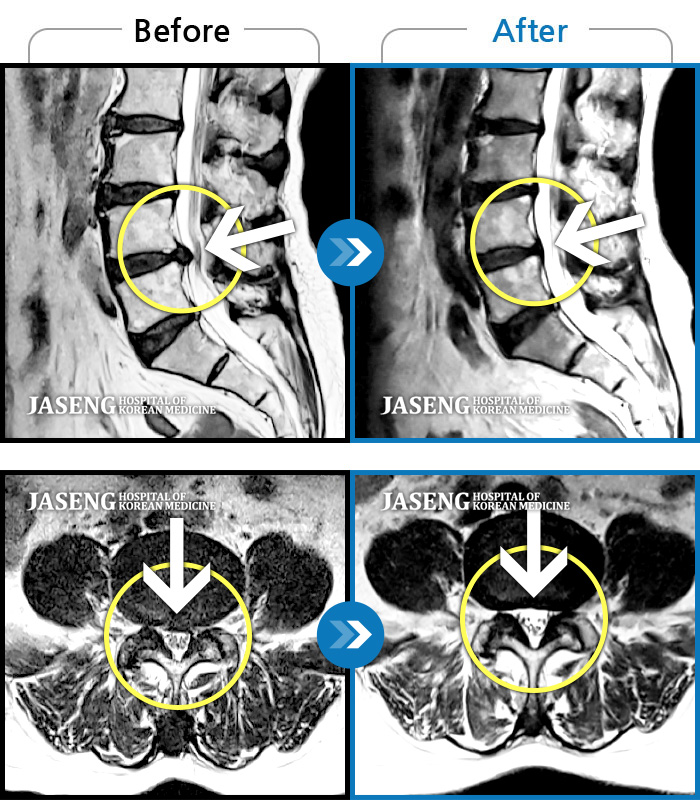

1,240 MRI ũ ʸ Ȯϼ.